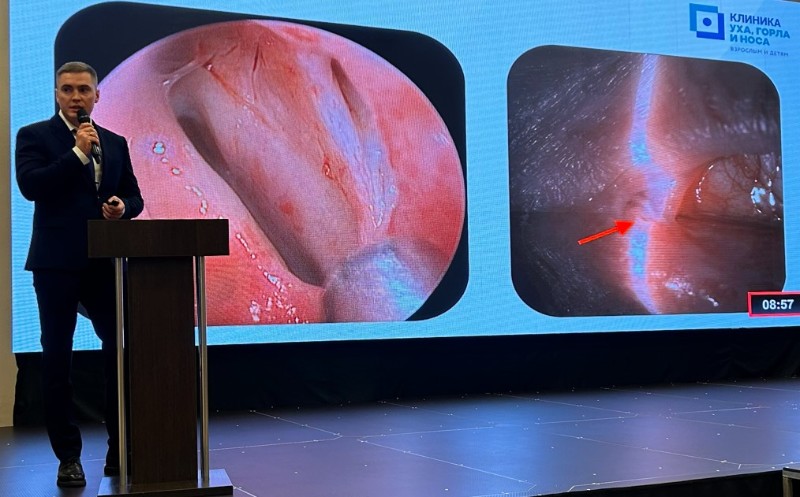

04.11.2025Якунин Сергей Александрович продемонстрирован передовой метод восстановления слезоотведения на офтальмологической конференции.

04.11.2025Якунин Сергей Александрович продемонстрирован передовой метод восстановления слезоотведения на офтальмологической конференции. -

21.10.2025Хирург-отоларинголог нашей клиники в Сочи провел первую в городе эндоскопическую операцию по устранению непроходимости слезных путей.

21.10.2025Хирург-отоларинголог нашей клиники в Сочи провел первую в городе эндоскопическую операцию по устранению непроходимости слезных путей. -